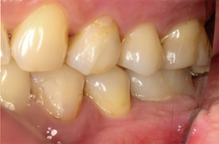

Intra-Oral Pictures (Before)

- Erosion severity: ACE Class Class III

- Reduced occlusal vertical dimension

Our goal was to restore his smile as conservatively as possible, in line with his request to avoid full-crown preparations unless absolutely necessary. To achieve this, we planned a combination of veneers, veneerlays, and onlays, along with limited orthodontic intervention.